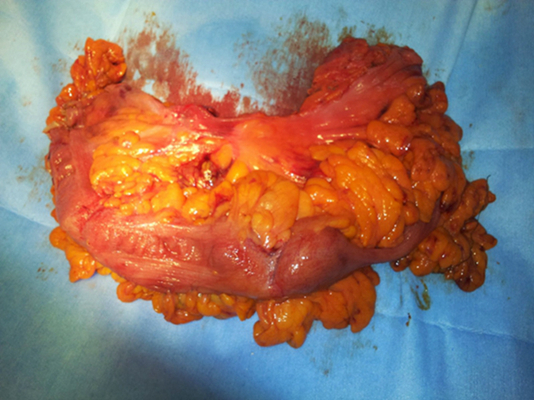

結腸癌症狀 (37)

結腸癌症狀 (38)

結腸癌症狀 (39)

結腸癌症狀 (4)

結腸癌症狀 (40)